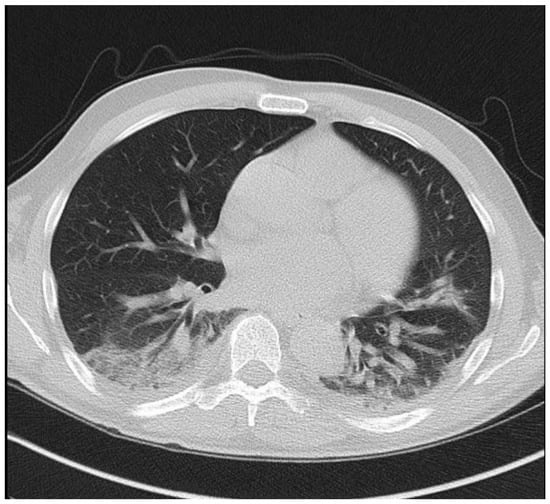

On 16 March, he presented to the emergency department with high fever and dry cough. He reported no contact with a coronavirus-infected patient or travel history. His symptoms started fivedays before presentation and rapidly deteriorated on the day of admission. On physical examination, he was tachypnoeic with SatO2: 93%. The throat swab sample for SARS-CoV-2 (RT-PCR) was positive, and the patient was transferred to a referral hospital for COVID-19. His blood tests revealed a white blood cell count of 5800 × 109/L (neutrophils 58%, lymphocytes 36%), a C-reactive protein level of 65 mg/L (nr < 5) and slightly elevated d-dimers. A hepatic panel, LDH value and procalcitonin level were normal. A chest CTscan showed diffuse bilateral infiltrates (Figure 1). Besides respiratory support with oxygen therapy, treatment with hydroxychloroquine (200 mg bid) and ceftriaxone was initiated. The patient’s clinical status deteriorated rapidly, and, twodays later, he was transferred to the intensive care unit (ICU), where he was put on mechanical ventilation due to respiratory failure. Azithromycin (500 mg od for seven days) was added in the ICU. Remdesivir was not administered because of renal impairment (peak creatinine level of 2.8 mg/dL, corresponding to an eGFR of 23 mL/min/1.73 m2 by the CKD-EPI equation). The patient remained hemodynamically stable without vasopressors and maintained a satisfactory urine output despite a transient renal function deterioration. His respiratory function gradually improved, and he was discharged from the ICU after seven days and transferred to the rehabilitation unit. Meanwhile, a second CT scan on the 16th day of hospitalization showed a significant improvement of the lung lesions. After 25 days of hospitalization, he was discharged, and he remains in good clinical condition. His creatinine level has returned to 1.4 mg/dL.

Figure 1. Multifocal ground glass density lesions were observed on a CT scan in the lower lobes bilaterally.